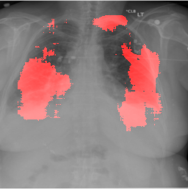

4.2.2 Pulmonary Edema Localization

In order to test the effectiveness of the localization procedure in areas other than the heart region, we chose pulmonary edema which occurs in the lung region. Also, pulmonary edema is detected by the net like white structure in the lung area. No anatomical shape change is associated with the abnormality. We have found that the localization is obtained best when the ROIs of lungs are taken to compute the map. Following the scheme in section 3.4, localization experiment on pulmonary edema is performed as shown in Fig. 8. It has been observed that the classifier is not sensitive to the fine features like septal or Kerley B lines. The localization is mainly obtained in the lung region where excess fluid is observed. Some localization regions are outside the lung region which occurs primarily for the fact that, even though the occlusion center is outside the lung, it occludes lung region and thus the probability drop occurs.

In a similar fashion, additional localization results for Pulmonary Edema is shown in Fig. 13. In Fig. 13(a) and (b) localization of two examples of CXRs with Pulmonary Edema is shown. As stated earlier the classifier localizes in the lung region. This is not the case when normal images are used to localize Pulmonary Edema as seen in Fig. 13(c) and (d). The localizations are obtained in random dense locations such as the sternum or heart. Like the cardiomegaly case, the histogram averages for CXRs with pulmonary Edema (Fig. 13(e)) shows a sensitivity toward pulmonary edema detection while the normal CXRs shows a spread out detection. It is interesting to note that, in the histogram of normal images high probability (¿0.85) is non-existent, thus ensuring low false positive rate. In the test set none of the normal images have been diagnosed as Pulmonary Edema. The failure cases are shown in Fig. 12. These CXRs are with Pulmonary Edema. However, the localization algorithm shows that one of them localizes in lungs whereas the other one shows a localization pattern similar to that obtained in normal CXRs.